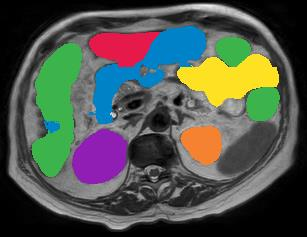

Vision transformers, with their ability to more efficiently model long-range context, have demonstrated impressive accuracy gains in several computer vision and medical image analysis tasks including segmentation. However, such methods need large labeled datasets for training, which is hard to obtain for medical image analysis. Self-supervised learning (SSL) has demonstrated success in medical image segmentation using convolutional networks. In this work, we developed a \underline{s}elf-distillation learning with \underline{m}asked \underline{i}mage modeling method to perform SSL for vision \underline{t}ransformers (SMIT) applied to 3D multi-organ segmentation from CT and MRI. Our contribution is a dense pixel-wise regression within masked patches called masked image prediction, which we combined with masked patch token distillation as pretext task to pre-train vision transformers. We show our approach is more accurate and requires fewer fine tuning datasets than other pretext tasks. Unlike prior medical image methods, which typically used image sets arising from disease sites and imaging modalities corresponding to the target tasks, we used 3,643 CT scans (602,708 images) arising from head and neck, lung, and kidney cancers as well as COVID-19 for pre-training and applied it to abdominal organs segmentation from MRI pancreatic cancer patients as well as publicly available 13 different abdominal organs segmentation from CT. Our method showed clear accuracy improvement (average DSC of 0.875 from MRI and 0.878 from CT) with reduced requirement for fine-tuning datasets over commonly used pretext tasks. Extensive comparisons against multiple current SSL methods were done. Code will be made available upon acceptance for publication.